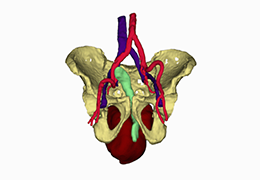

ANYTHINK 经导管主动脉瓣膜置换术分析系统